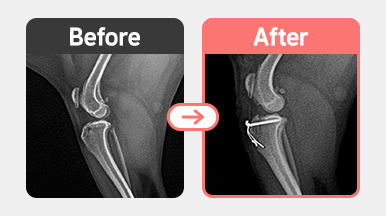

진단명 : 양측 슬개골 탈구 2기 / 중등도의 연골 마찰음

치료내용 : 양측 슬개골 탈구 교정술 (Trochleoplasty + TTT + 연부조직 정리)

정형외과 검사 결과 양측 슬개골 탈구 2기와 연골 마찰음이 확인되었습니다.

우측은 구조적 변형과 연골 마모가 더 심해 대퇴고랑 성형(Trochleoplasty)+경골조면 전위(TTT) +

늘어진 연부조직 교정(관절낭 부분 정리)을 시행했습니다.

좌측도 동일하게 홈 성형과 TTT를 진행하여 양측 슬개골의 정렬 및 안정성을 확보하였습니다.

수술 후 양측 정복 상태는 안정적으로 유지되며 보행 회복도 점차 개선되고 있습니다.